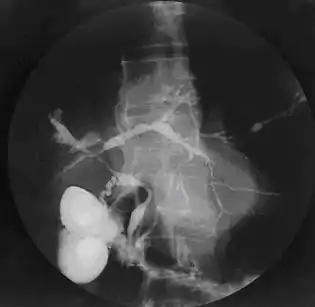

![]() Colangiograma de una colangitis esclerosante primaria. | ||

El diagnóstico de la colangitis esclerosante primaria se realiza con la demostración de las alteraciones típicas del árbol biliar, que incluyen zonas estenóticas (estrecheces) y dilataciones multifocales. El diagnóstico de elección hasta hace algunos años era realizado a través de una colangiografía retrógrada endoscópica (CPRE), pero actualmente la colangiografía por resonancia magnética (colangioresonancia) prácticamente ha reemplazado a la colangiografía retrógrada. Esta última se reserva para casos de duda diagnóstica y para cuando se planifica una intervención sobre la vía biliar.